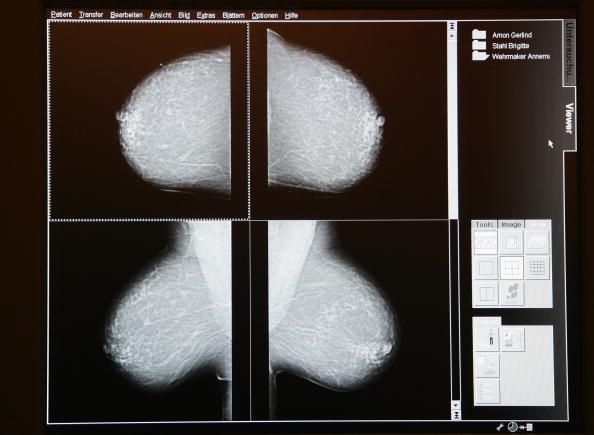

Directrices sobre la frecuencia para detectar diferentes tipos de cáncer, lo que pone a prueba a utilizar, ya qué edad comenzar han evolucionado en los últimos años. En algunos casos, en particular la mamografía para el cáncer de mama, los diferentes grupos no están de acuerdo sobre cuándo iniciar el cribado y la frecuencia para hacerlo. Esto ha llevado a la confusión, por lo que la ACP decidió revisar las directrices y encontrar las estrategias menos intensas pruebas con el consenso más amplio. El objetivo es beneficiar a la mayor cantidad de personas que no tienen un exceso de pruebas, lo que puede aumentar los costes y que a menudo conducen a falsos positivos y falsas alarmas.

Para el cáncer de mama, la ACP aconseja que las mujeres de 50 a 74 tienen una mamografía cada 2 años y que los médicos discutir los pros y los contras de la mamografía con los pacientes de 40 a 49 años de edad.